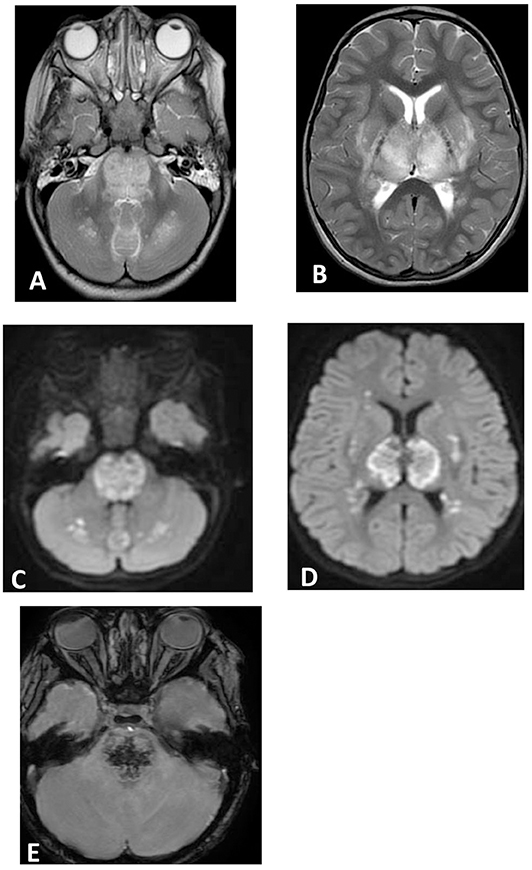

A total of 14 patients with ANEC were identified; two patients were excluded due to the inability to meet the ANEC radiological criteria. Patients' ages ranged from 10 months to 6 years (mean 30.92 months, median 22 months, standard deviation 20.63). Nine patients (75%) were female. All patients presented with preceding febrile illness in the form of upper respiratory tract infection (URTI) symptoms, or gastrointestinal symptoms in the form of vomiting or diarrhea, and altered level of consciousness. Seizures were the initial presentation in eight cases (66.7%). Brain imaging was carried out using Axial, Sagittal, and Coronal T1,T2, FLAIR, diffusion, and susceptibility weighted images which showed characteristic high signal intensity on axial T2 and FLAIR with variable degree of involvement of both thalami in all cases. Diffusion restriction was also seen, while the susceptibility sequence showed dark signal intensity with blooming, indicating hemorrhagic changes. Out of 12 patients, five (41.7%) had brainstem involvement. Follow up brain MRIs were done 2–3 months after the initial presentation, which showed signs of improvement on 33.3%, and 66.7% (n = 8) showed no signs of improvement. The clinical and radiological presentations are summarized in Tables 1, 2. Figures 1–4 show brain MRIs for selected patients.

Figure 2. Brain MRI. Axial T2 (A,B), diffusion (C,D), and susceptibility (E) weighted images. There are swelling and abnormal high signal intensity of pons, bilateral cerebellar white matter (A), both thalami, and bilateral putamen (B) with diffusion restriction (C,D) and dark signal intensity with blooming in the pons (E).